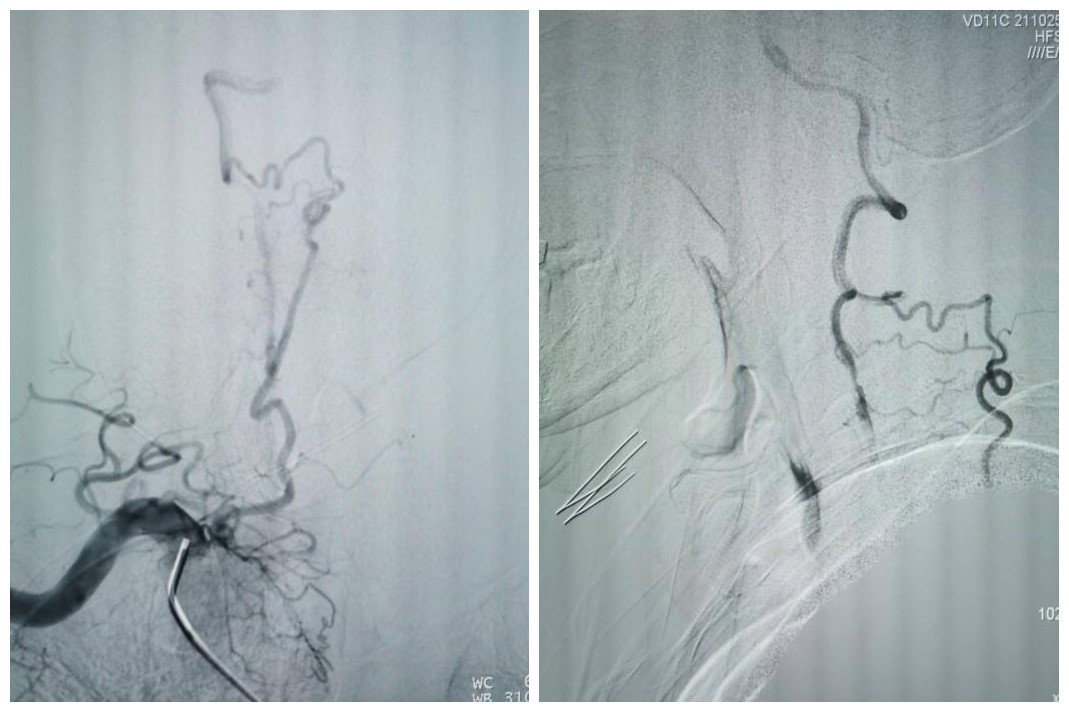

受呼吸起伏波动的影响,椎动脉开口狭窄是动脉粥样硬化好发的部位之一,也是支架成形术后支架内再狭窄的好发部位。这个短小的病变对于神经介入医师来说,常常是最青睐的支架手术部位。然而,该患者延伸至V2远端的长节段慢性闭塞病变,闭塞长度接近10cm,尤其是闭塞近段无残端的病变,常常会成为脑与心脏之间的“天堑”,使神经介入医师望而却步,即使眼看着患者的临床病情在进展,常常也是束手无策。

最终,在患者入院第4天,张桂莲教授带领的介入团队选择局麻条件下为患者成功实施了神经介入领域的高难度手术—左侧无残端椎动脉长节段慢性闭塞再通术。因术前清晰的影像显影及准确的体外定位标记,左侧优势椎动脉顺利开通,手术耗时仅仅约90分钟。术中及术后患者配合良好,无任何不适,术后在介入准备室,张桂莲教授向患者女儿详细告知手术过程及患者目前状况,患者女儿喜极而泣,多次向介入团队表示感谢。

双侧椎动脉闭塞是“天堑”,其所导致的后循环缺血事件是“天灾”,严重影响患者生活质量,甚至随时危及患者生命。无残端的双侧椎动脉慢性闭塞再通,是神经介入领域的最高难度手术之一,其原因在于根本无法确定手术位点。面对患者及家属的信任,我院张桂莲主任领导的神经内科介入团队与李晓会教授带领的影像学团队不忘初心、紧密合作、敢于挑战、乐于奉献,最终不负患者及家属重托将无残端长节段椎动脉闭塞的“天堑”变为后循环正常血流的“通途”。